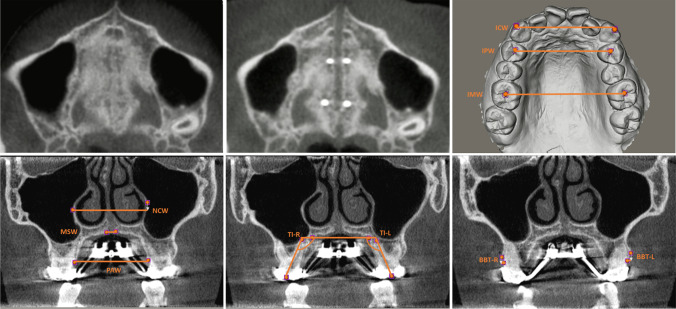

The measurements were taken at T0 (see: Fig. 6a) and T1 (see: Fig. 6b). The transverse measurements were measured along the X-axis, while the vertical measurements were measured along the Y-axis. The primary outcome measure was the total transverse maxillary expansion at the level of the upper first molar and first premolar, defined as the change in intermolar width (IMW) or interpremolar width (IPW) between T1 and T0, respectively. The change in intercanine width (ICW) was measured as well (see: Fig. 6c). The total transverse maxillary expansion was the sum of skeletal expansion, alveolar expansion, and dental expansion. Skeletal expansion was defined as the midpalatal suture width (MSW) measured at T1. Alveolar expansion was defined as the change in palatal alveolar width (PAW) between T1 and T0, minus the MSW. Dental expansion was calculated by subtracting the skeletal expansion and the alveolar expansion from the total transverse maxillary expansion. The nasal cavity width (NCW) and the nasal cavity expansion (T1-T0) were also measured (see: Fig. 6d). The measurements were taken in the coronal plane on the CBCT at the level of the buccal groove of the first molar or the buccal cusp tip of the first premolar. Detailed descriptions of the measurements are shown in Table 1. The success rate of the treatment was the percentage of patients achieving the required maxillary width.

Fig. 6.

The hard palate at T0 and T1, and skeletal and dentoalveolar measurements on CBCT and IOS. (A: upper left) Hard palate at T0, before midpalatal suture separation, on an axial CBCT slice. (B: upper middle) Hard palate at T1, with separated midpalatal suture, on an axial CBCT slice. (C: upper right) Measurement of IMW, IPW, and ICW on an intra-oral scan. (D: lower left) Measurement of MSW, PAW, and NCW on a coronal cross-sectional CBCT slice through the buccal groove of the M1. (E: lower middle) Measurement of TI left and right on a coronal cross-sectional CBCT slice through the buccal groove of the M1. (F: lower right) Measurement of BBT left and right on a coronal cross-sectional CBCT slice through widest portion of the mesiobuccal root of the M1

The secondary outcome measures, assessing dental and periodontal side-effects, were tooth inclination (TI), as a measure of angular dental tipping (see: Fig. 6e), clinical crown height (CCH), as a measure of gingival recession, and buccal bone thickness (BBT), as a measure of buccal bone loss. These measurements were taken at T0 and T1 at the level of the first molar and first premolar on the left (L) and right (R) sides and mean values were used for statistical analysis. BBT at the first molar was measured at the mesiobuccal root because, given its greater proximity to the maxillary buccal alveolar cortex, it was found to be more prone to significant changes than the distobuccal root (see: Fig. 6f) [10]. Lastly, treatment duration of the expansion was recorded as the number of days from the first to the last day of activation of the MARPE appliance.